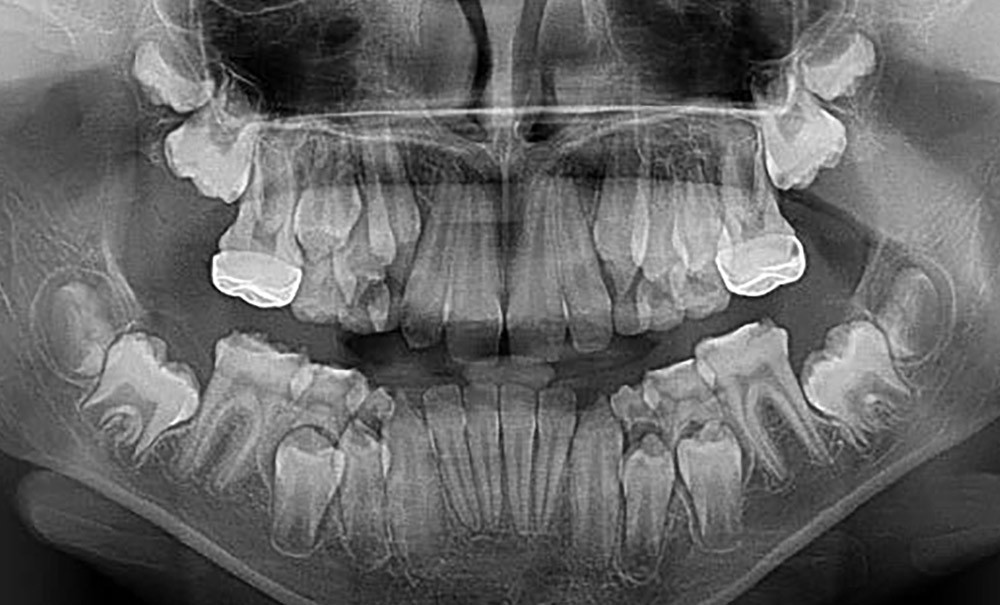

Et si les dents n’étaient pas celles que l’on attendait ? Parcours d’un enfant présentant des anomalies du développement dentaire à Marseille

L'arrivée des dents est un moment important dans la croissance de l’enfant. Les parents sont très attentifs à l'arrivée de toutes les incisives temporaires, bien blanches, en bonne position. Plus tard, l’enfant lui-même surveille la chute des dents temporaires et leur remplacement par de jolies dents comme les autres ! Mais la nature ne suit pas toujours le programme attendu…